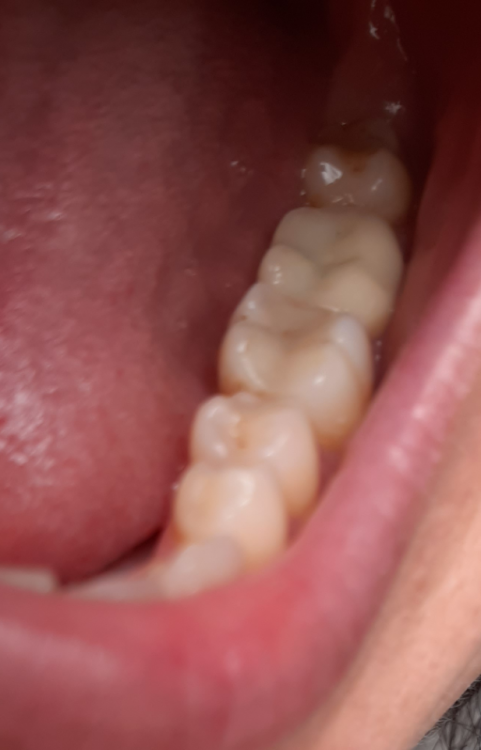

Лана-Лана Опубликовано 1 октября, 2021 Поделиться Опубликовано 1 октября, 2021 Добрый день уважаемые врачи, это опять я с продолжением темы, не знаю как лучше продолжать старую или начать новую тема( заранее извиняюсь) . Поставили мне коронку ( 7ка), при примерке я сразу обратила внимание что коронка ниже чем мои зубы, вернее бугры очень низкие и плоские , зуб практически как пенек, но ортопед сказал что у меня так и был свой видимо низкий , посмотрела на слепки и там все хорошо с этой коронкой. Я доверилась врачу, установили. Но дома я положила на зуб тонкую атласную ленту закрыла рот и она вытащилась ..ещё более менее на контакте с шестеркой а на контакте с восьмым зубом ну практически около десны..и теперь при жевании твердого немного больно десну в той области где коронка совсем низкая. Сказать что я расстроилась ничего не сказать, коронка цирконевая дорогая, что за криворукие техники... Что теперь делать? Может зуб чуть поднимется? Оцените если можно по фото...прилагаю так же снимки до депульпации зуба и после ,видно что он практически одного размера по высоте с другими зубами. И ещё момент в моем случае так неизбежна была вкладка? Почему врач всегда настаивает на вкладке? У меня что сильное разрушение зуба? Штифт ни как не хочет ставить. Цена то в два раза дороже выходит . Ссылка на комментарий

Лана-Лана Опубликовано 1 октября, 2021 Автор Поделиться Опубликовано 1 октября, 2021 (изменено) Это другой был зуб...так контакта нет с соседнем зубом и пища набивается, форма да не нравилась но я с этим смирилась и благо не в зоне улыбки!!! здесь другая проблема нет контакта с верхними зубами, и очень низкий и больно десну когда что то твердое попадает.. Как бы за 30 т за коронку ждёшь более лучшего результата и более точного исполнения ... Изменено 1 октября, 2021 пользователем Лана-Лана Ссылка на комментарий

Лана-Лана Опубликовано 1 октября, 2021 Автор Поделиться Опубликовано 1 октября, 2021 Ещё вопрос второй, по моим фото - это вообще коронка CAD/CAM стоит? Почитала что такие коронки вытачивает компьютер и очень точно , и что то я засомневалась теперь те ли коронки мне поставили..даже анотомических бугорков нет, это все врач в течении часа во рту после установки там подпиливала что бы она не была пеньком... Ссылка на комментарий